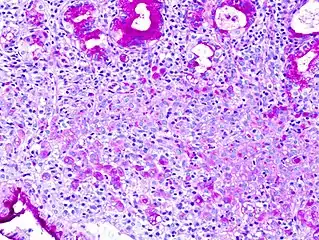

The name of the cell comes from its appearance; signet ring cells resemble signet rings. They contain a large amount of mucin, which pushes the nucleus to the cell periphery. The pool of mucin in a signet ring cell mimics the appearance of a finger hole and the nucleus mimics the appearance of the face of the ring in profile.

Signet ring cells (magenta) stained with PAS in a gastric signet ring cell carcinoma.